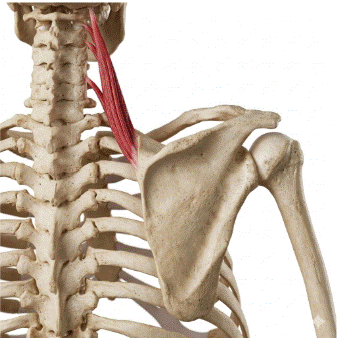

Elevador de la escápula: puntos gatillo y cervicalgia crónica

El elevador de la escápula es uno de los músculos más frecuentemente implicados en el dolor cervical crónico y, sin embargo, uno de los menos identificados correctamente por los propios pacientes. Su localización profunda en la región lateral del cuello, su patrón de dolor referido hacia el ángulo superior de la escápula y la facilidad […]